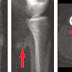

Secara kasar kista tulang adalah tumor jinak yg terdiri dari pembungkus serupa balon berisi cairan di dalamnya yg terdapat di dalam tulang. paling sering di tulang panjang seperti tulang lengan atas atau tulang paha namun bisa aja di tulang iga dan dapat menyebabkan tulang tsb patah/rapuh. penanganannya sih biasanya diangkat dg operasi namun ada kalanya yg kecil bisa sembuh sendiri.

Gejala kista tulang:

Nyeri (biasanya ringan dan intermiten) adalah gejala yang paling umum terjadi. Daerah yang terlibat mungkin terlihat bengkak. Pembengkakan akan cenderung meningkat sampai lesi diobati. Jika lesi terletak di kolom vertebral, dapat menyebabkan tanda dan gejala kompresi sumsum tulang belakang (yang dapat mengakibatkan kelemahan kaki, disfungsi usus atau kandung kemih).